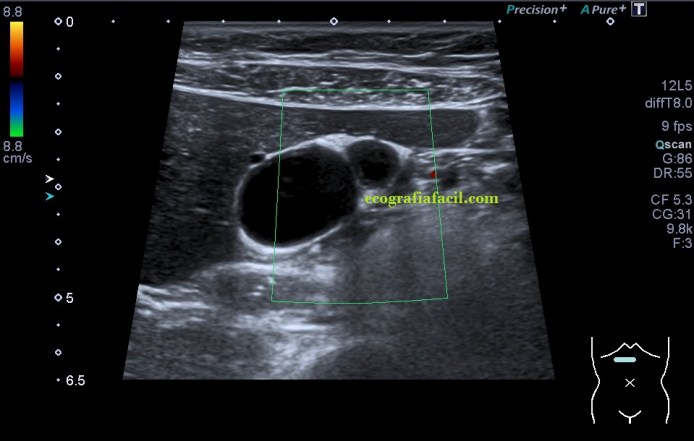

La paciente presentaba una vesícula muy normal, pero escondía tesoros, dos concretamente. Tras un aspecto sacular y anecoico, con una transmisión de sonido muy bonita, se presentaban dos aspectos ecográficos, primero te enseño las imágenes y luego te explico, ¿quieres?…

En la imagen 1 la ecoestructura era absolutamente normal, sacular, alargada y anecoica en longitudinal, pero en la imagen 2 se presenta una estructura en una forma anómala, variante de la normalidad, que en ecografía se denomina «vesícula en gorro frigio», su aspecto recuerda a este tipo de gorros de forma cónica con punta curvada que históricamente han acompañado a la humanidad en multitud de situaciones, te dejo el enlace (cultura general) por si te apetece leer un poco…es curioso.

Sumado a esta peculiar presentación encontramos que en la curvatura sacular, en el fundus de la vesícula, «en la punta» que se objetiva en la imagen 2, percibí como si la pared en ese punto estuviera ligeramente engrosada, pero no terminaba de verlo como yo quería así que cambié la sonda, de cónvex a lineal, adapté los parámetros o ajustes ecográficos y la imagen de la pantalla era preciosa, se veía la imagen sacular, muy definida, gracias a la alta frecuencia de la sonda lineal, con una definición muy importante que me permitió documentar como en la pared de la vesícula, imagen 4, existía engrosamiento mural. Se usa el cónvex virtual o trapezoidal, como ajuste que permite ampliar el scan range de la pantalla con el uso de la sonda lineal.

Dicho engrosamiento, una vez revisada la historia clínica estaba descrito como adenomiomatosis, y ecográficamente era un engrosamiento mural, parcial (solo era en una porción de la vesícula), hiperecogénico y homogéneo, perfectamente visible en la imagen 4, señalada con una flecha amarilla fina.

En el doppler (imagen 5) no había actividad, pero esto hay que comprobarlo siempre ya que en ocasiones, la literatura habla de actividad vascular del engrosamiento mural. Además podemos encontrar sendos artefactos ecográficos, como el aliasing y la cola de cometa, provocados por estos focos adenomiomatosos, que en este caso específico, no se objetivaron, una pena…la verdad.